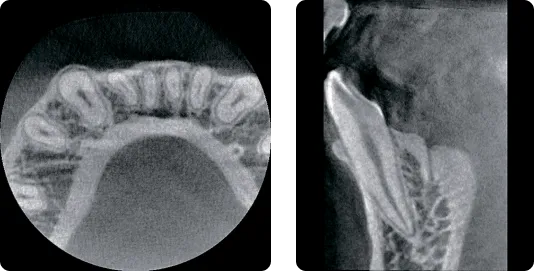

Свободный FOV

Вы можете наглядно видеть на чём фокусируетесь, благодаря свободному FOV со световым наведением.

Видимый рентгеновский указатель RAYSCAN указывает на область сканирования. Пользователь может удобно регулировать FOV* в соответствии с зоной своего интереса.

Англ. яз. FOV-Field Of View (Поле зрение)